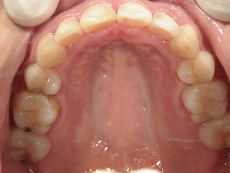

● ツインフォース

下顎が後退している方に用いられる装置です。後ろにずれている下顎を前方(本来の位置)に移動させ、噛み合わせを整えます。

上顎に比べ、下顎が著しく後退しています。

上の歯と下の歯を斜めに繋ぐようにツインフォースという装置を装着します。装置の力で、顎が前方へ押し出されてきました。

顎の移動が終了しました。装置を外して、今後はワイヤーを使用して歯列を治します。

矯正治療後の後戻りを想定して、あえて必要量を越えた顎の移動を行います。